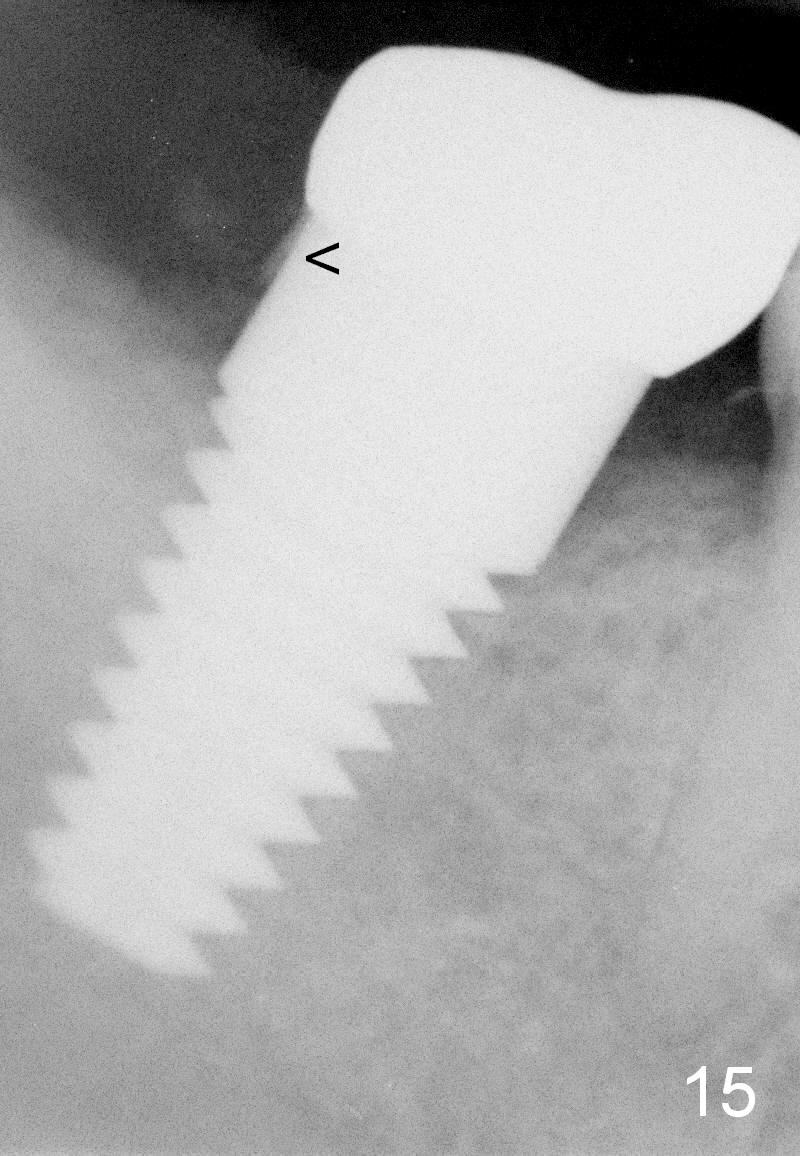

The tooth #31 of a 38-year-old lady has endo perio disease (Fig.1). Due to the large periapical lesion, there will be no solid (new) bone available for primary stability of an immediate implant (Fig.2: 7x17 mm). Yellow dashed line represents the upper border of the Inferior Alveolar Canal (IAC). Infiltration anesthesia is administered first. The mesiodistal widths of the root of the extracted tooth are 10 and 7 mm at the coronal and apical ends, respectively; the buccolingual ones 7 and 5 mm; the length 17 mm (Fig.3). The socket appears much larger than the root (Fig.4). To prevent paresthesia, no drills are used. Instead, a series of tap drills (6,7,8x17 mm) are sequentially inserted into the socket. The largest tap (Fig.5 T; 8x17 mm) binds to the socket securely with separation from IAC. Block anesthesia has to be administered before removal of the tap. A tapered implant (8x17 mm) is placed with insertion torque greater than 60 Ncm (Fig.6 I); allograft mixed with Osteogen is placed around the implant (*). Collagen dressing covers the opening of the remaining socket. The wound is protected with perio dressing, which is partially secured by an abutment (A in Fig.6). No paresthesia is reported by the patient a few hours postop.